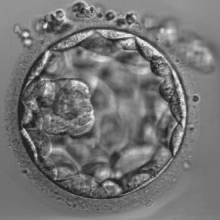

By Jayne Mullen, Scientific Director Victoria When embryos reach the blastocyst stage on Day 5,…